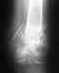

Спасибо что ответили....укорочение после наложения аппарата илизарова есть 5 см...в кургане мне и пытались замкнуть сустав, но консолидации не добились...а вскрывать они боятся...проблема обсуждалась...но я готова пойти на риск пусть лучше заражение и тд чем мучится болями столько лет...возможно у Вас есть информация какие клиники в порядке может эксперимента возьмутся что либо сделать..снимок с отправляла Вам с тех пор по заключению наших врачей при прохождении МСЭК ставят диагноз не сросшийся перелом..может что то посоветуете куда можно обратится.Заранее благодарна.